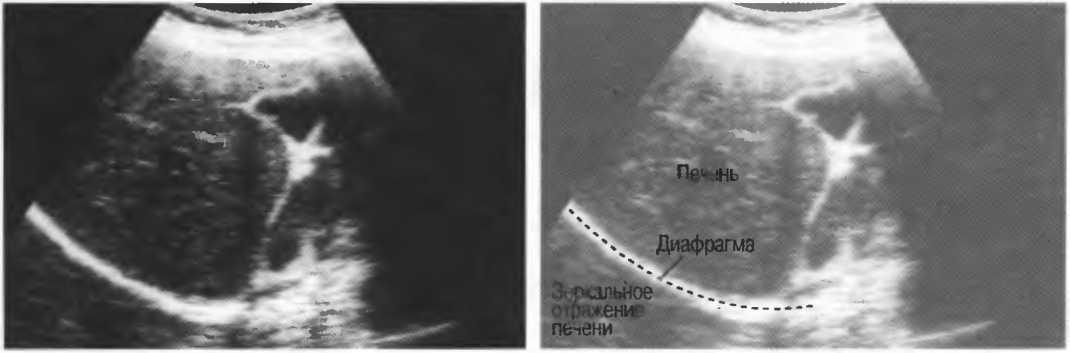

Эффект зеркала |

Отражение всех или почти всех ультразвуковых волн некоторыми тканями или границами раздела сред. например границей «диафрагма-легкие». Эффект зеркала иногда создает артефакт зеркального отражения, дающий удвоение изображения. |

Череп плода, дифрагма, стенки сосудов, соединительная ткань являются примерами зеркальных отражателей (рис. 6).

Рис.6. Сагиттальный срез печени: имеется очень сильное (зеркальное) отражение от диафрагмы, являющейся таким мощным отражателем, что изображение печени повторяется за ней. Ультразвуковые волны проходят через печень после излучения, затем повторно — после отражения от диафрагмы, затем — от поверхностей тканевых структур.